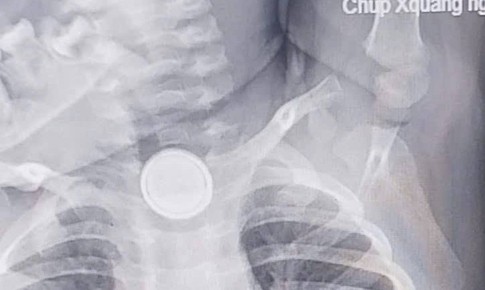

Bé trai 11 tháng tuổi nuốt mảnh vỡ ống thuốc, dị vật cắm sâu vào thực quản

Camera bệnh viện - 04/04/2025 18:33SKĐS - Trong lúc chơi đùa, bé trai 11 tháng tuổi ở Nghệ An bất ngờ cắn và nuốt phải mảnh vỡ ống thuốc tiêm. Dị vật sắc nhọn cắm vào thực quản khiến cháu đau đớn, la khóc dữ dội.